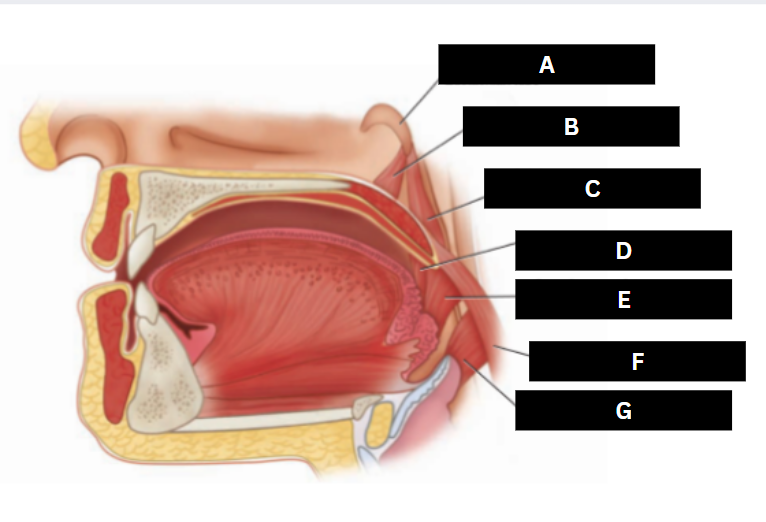

Eustachian tube

A

Levator veli palatini

B

Salpingopharyngeus

C

Palatoglossus

D

Superior pharyngeal constrictor

E

Palatopharyngeus

F

Middle pharyngeal constrictor

G